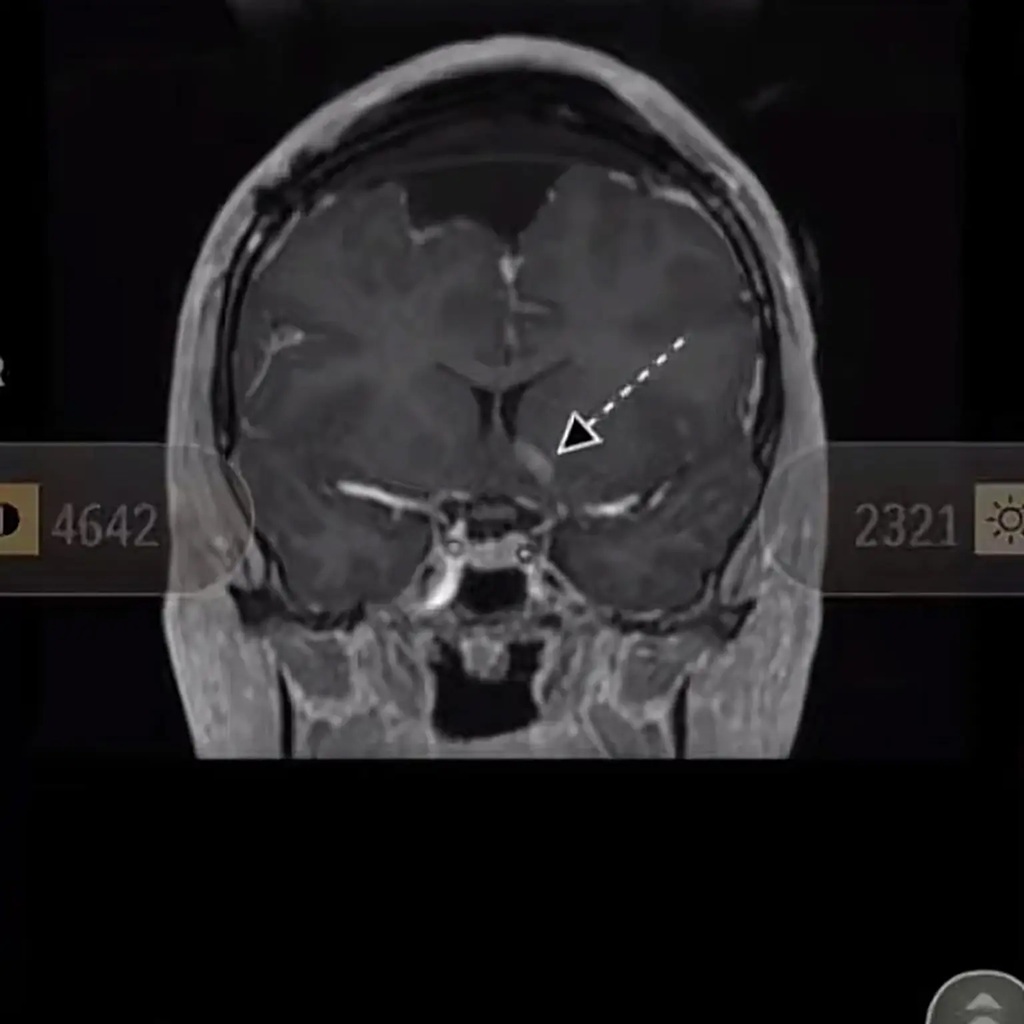

मैरी ने लिखा, "मेरी हालत बहुत खराब है। मेरे कई ऑपरेशन और इलाज हुए हैं। मैं हमेशा से निष्ठावान रही हूं। जब तक यह सब नहीं हुआ, मैं उसके लिए खाना बनाती रही। वह पूरा यकीन है कि मैं अधिकारों के प्रति मर चुकी हूं। मुझे लगता है कि मेरे पास एक मौका है।" मैरी ने अपने MRI स्कैन की फोटो भी शेयर की। इसके साथ ही यह भी शेयर किया कि उसके पति ने क्या संदेश दिया है।

फोटो- मैरी के एमआरआई स्कैन की तस्वीर